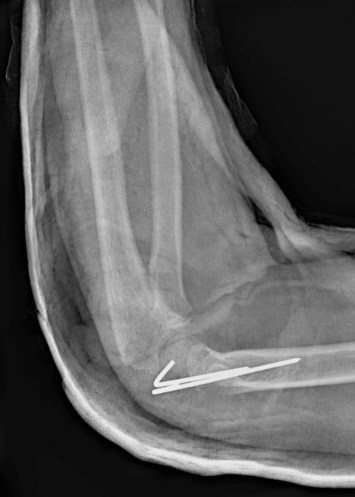

Загальна рентгенографія

Педіатрія